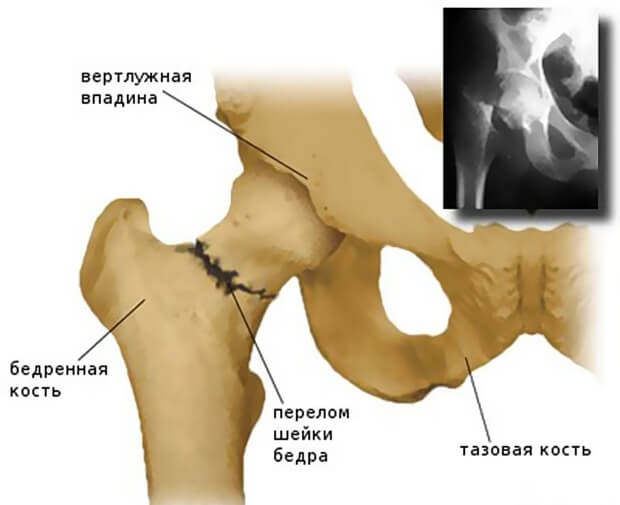

Тазовое кольцо образовано тремя парными тазовыми костями (лобковой, подвздошной и седалищной) и расположенным сзади крестцом. 3 тазовые кости с каждой стороны разделены между собой тонкими костными швами и неподвижны относительно друг друга.

Спереди лобковые кости сочленяются, образуя лобковый симфиз. Сзади подвздошные кости крепятся к крестцу с помощью крестцово-подвздошных сочленений.

В наружно-боковой области все 3 тазовые кости участвуют в образовании вертлужной впадины (части тазобедренного сустава).